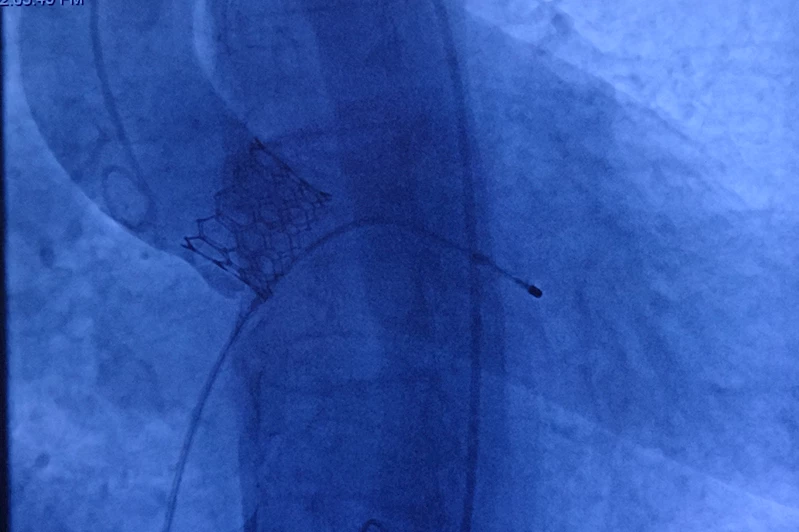

"Nefes darlığı, göğüs ağrısı ve son dönemde ciddi baş dönmeleri yaşayan hastamızın ekokardiyografisinde ileri derece aort darlığı tespit ettik. Açık ameliyatın yüksek riskli olması nedeniyle, kalp cerrahları ile yaptığımız değerlendirme sonucunda TAVI yöntemini uygulama kararı aldık. Anjiyo yöntemiyle kalp kapağını başarılı bir şekilde değiştirdik ve hastamız sağlığına kavuştu."

Her ay ortalama 8 ila 10 hastaya bu yöntemin uygulandığını belirten Pekdemir, "Kapalı yöntemle yapılan bu işlem, hasta için son derece konforlu. Açık kalp ameliyatında olduğu gibi göğüs kafesi kesilmiyor, kalp durdurulmuyor ve sadece kasıktan küçük bir delikle girilerek işlem gerçekleştiriliyor. Hastalar ikinci gün servise alınıyor ve genellikle üçüncü gün taburcu ediliyor. Özellikle yaşlı hastalar için bulunmaz bir yöntem" şeklinde konuştu.